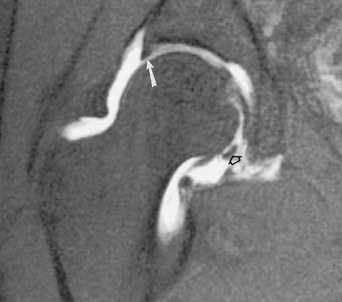

![]() |

FIGURE 4-28 Coronal MR arthrogram image demonstrating the normal triangular shape of the superior labrum (arrow) and the transverse ligament inferiorly (open arrow).

P.167

FIGURE 4-29 Coronal MR arthrogram image demonstrating a superior labral tear (arrow).